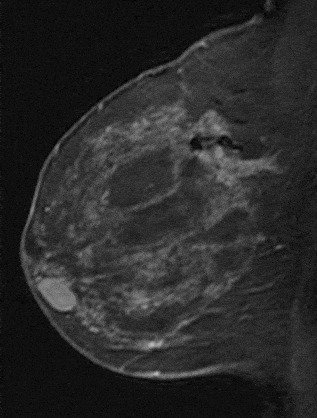

The shape and margins of masses can be described. Mass shape can be described as round (Fig. 2), oval (Fig. 3) or not otherwise specified (NOS). Margins of masses are smooth (Fig. 4), lobulated (Fig. 5), irregular (Fig. 6) or spiculated (Fig. 7). Spiculated or irregular masses are suspicious for carcinoma whereas a smooth margin is more suggestive of a benign lesion and lobulated borders are of intermediate concern. It is important to realize that margin analysis is dependent on spatial resolution and that even irregular borders can appear relatively smooth when insufficient resolution is used. Therefore, carcinoma may present with benign imaging features on MR imaging, particularly when small. In general, margin and shape analysis should be performed on the first post-contrast image to avoid washout and progressive enhancement of the surrounding breast tissue, which could obscure lesion analysis.

Figure 2. Round mass. Pathology – Fibroadenoma.